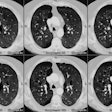

Bronchiolitis obliterans:

The patient shown below had experienced a severe right lower lobe haemophilus influenza pneumonia the preceding year, but had persistent pulmonary complains. The inspiratory CT images reveal bronchiectatic changes involving the bronchi to the anterior and medial basal segments of the right lower lobe (yellow arrows). Expiratory images deomstrate air trapping in these same segments (white arrows). Air trapping is also evident in the medial segment of the right middle lobe. The findings are consistent with post-infectious bronchiolitis obliterans.